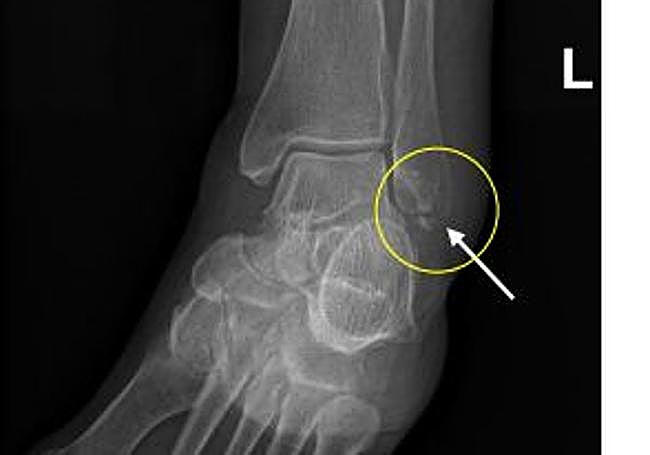

Tras caerse, la mujer tuvo que ser trasladada al Hospital de Salamanca en una ambulancia y allí se la atendió de urgencias. Salió del centro con el diagnóstico de una fractura fractura infrasindesmal en el peroné izquierdo. Se trata de una lesión grave en la zona de tendones de este hueso, ya casi en el tobillo.

Fractura que sufrió la viandante.

La víctima estuvo casi dos meses escayolada y cinco en rehabilitación, con muletas, hasta que en julio de 2023 le dieron el alta porque ya podía caminar bien. Tras lo ocurrido, presentó una reclamación por daños de 10.055 euros por los daños sufridos y las secuelas, un dolor permanente en el tobillo.